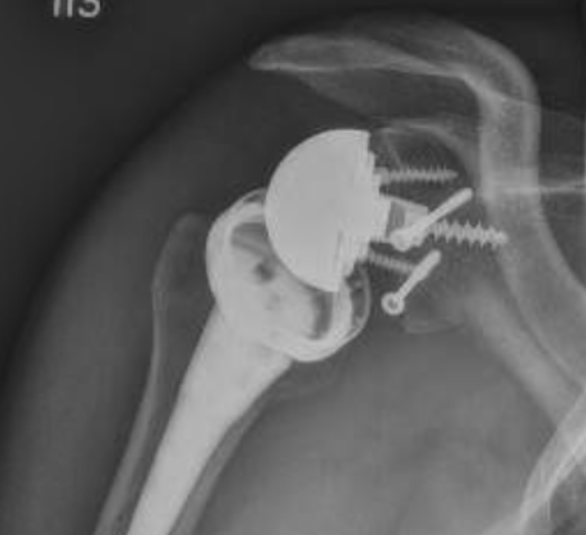

Loosening

Failed Glenoid Reverse TSRReverse TSR Loose Metaglene

Loose metaglene

Lysis around humeral and glenoid component